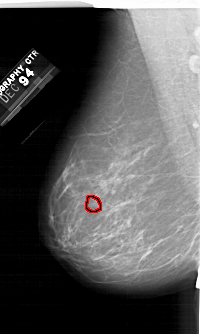

A_1245_1.LEFT_CC

LEFT_CC LINES 6856 PIXELS_PER_LINE 3811 BITS_PER_PIXEL 12 RESOLUTION 43.5 OVERLAY

FILE: A_1245_1.LEFT_CC.OVERLAY

TOTAL_ABNORMALITIES 1

ABNORMALITY 1

LESION_TYPE CALCIFICATION TYPE PLEOMORPHIC DISTRIBUTION CLUSTERED

ASSESSMENT 4

SUBTLETY 4

PATHOLOGY MALIGNANT

TOTAL_OUTLINES 1

BOUNDARY